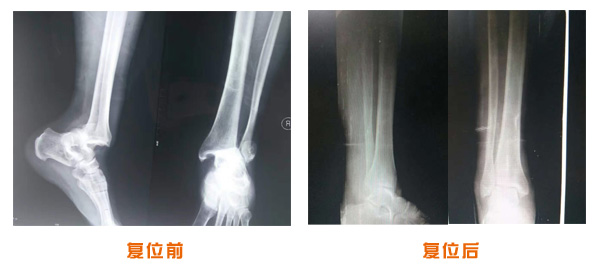

肥城市安駕莊梁氏骨科醫院是一所以梁氏手法正骨配合膏藥為特色的現代化專科醫院。

梁氏骨科術始創于清雍正年間,歷經八代,至今已有三百年歷史。據1929年泰安縣志載“梁瑞圖先生,字增生,號蓮峰,安駕莊人,精岐黃并發(fā)明接骨,凡跌打車凡跌打車軋皮不破而碎骨者......【詳細】 |